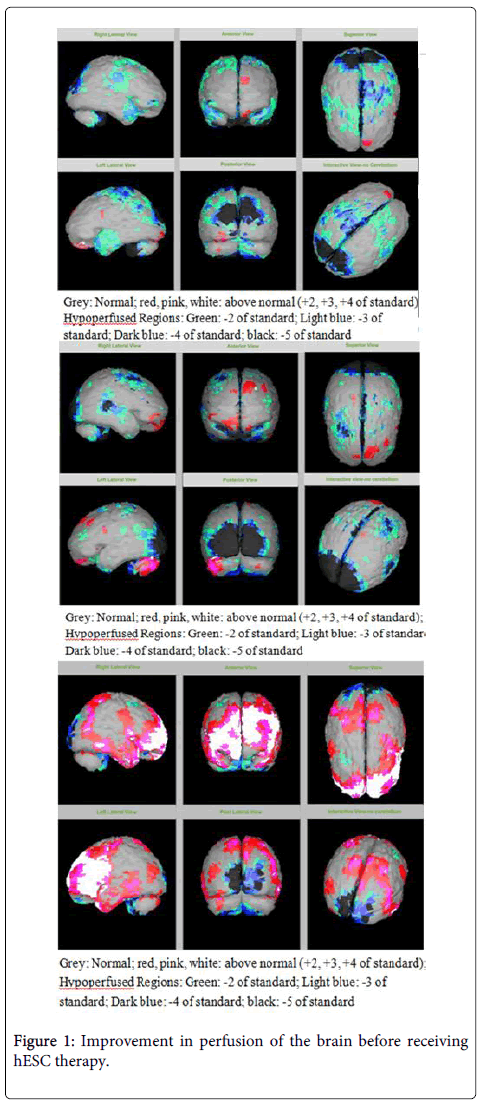

該患者的SPECT掃描如圖1和2所示。

圖1:接受hESC治療前大腦灌注的改善。

SPECT掃描

在研究開始和結束時,23名患者接受了SPECT掃描。在枕葉或額葉或雙葉中觀察到灌注不足。23例接受SPECT掃描的患者中,5例患者表現為枕葉灌注不足,7例患者表現為額葉灌注不足,11例患者表現為枕葉和額葉灌注不足。

總體而言,治療結束時,2名患者的灌注正常,18名患者(12名男性和6名女性患者)顯示灌注顯著改善(>60%),3名患者顯示灌注中度改善(30-60%)。大多數在接受hESC治療前額葉和枕葉嚴重低灌注的患者在接受 hESC 治療后情況有所改善。23名可獲得SPECT掃描報告的患者的GMFCS評分在hESC治療后有所改善(表2)。